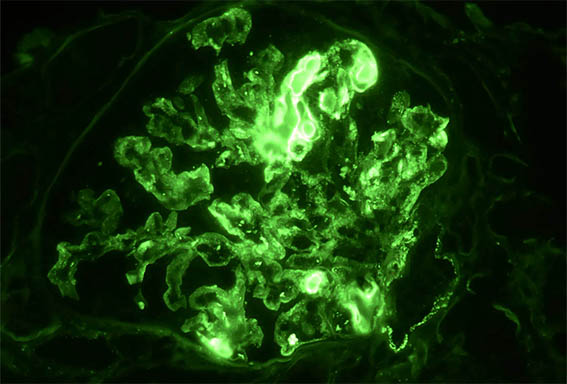

Figure 10. Direct immunofluorescence for IgG, X400.

Figure 11. Direct immunofluorescence for IgM, X400.

Figure 12. Direct immunofluorescence for C3, X400.

Figure 13. Direct immunofluorescence for C1q, X400.

Figure 14. Direct immunofluorescence for kappa light chains, X400.

Figure 14. Direct immunofluorescence for lamba light chains, X400.

Immunofluorescence for IgA: negative.